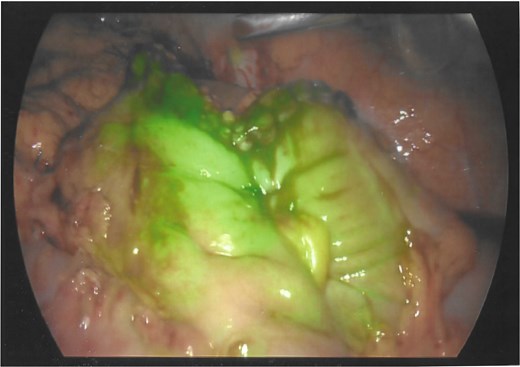

As a result, a laparoscopic left hemicolectomy was performed. The descending colon was medialised by incising the White line of Toldt from the proximal sigmoid colon, with dissection of splenocolic, phrenicocolic and the pancreaticocolic ligaments proximally. The colocutaneous fistula was identified during medialisation of the proximal descending colon and was excised (Fig. 1). There were chronic changes of inflammation and fibrosis around this region, without an abscess cavity. The distal transverse colon was then mobilised by dissecting the gastrocolic ligament to enter the lesser sac. The mobilised colon was then exteriorised through a midline laparotomy, the left colic and the left branch of the middle colic arteries were ligated and an extracorporeal side to side, functional end to end stapled anastomosis occurred using NTLC 75 mm blue reload stapler between the distal transverse and the distal descending colon. Indocyanide Green (ICG) angiography was used to confirm good perfusion at the anastomosis (Fig. 2). A well vascularised omental patch covered the remnant fistula tract on the lateral posterior abdominal wall. Postoperative recovery was uncomplicated. Histopathology was consistent with a fistula tract without evidence of malignancy.

Indocyanide green (ICG) angiography demonstrating good perfusion at the colo-colonic anastomosis.